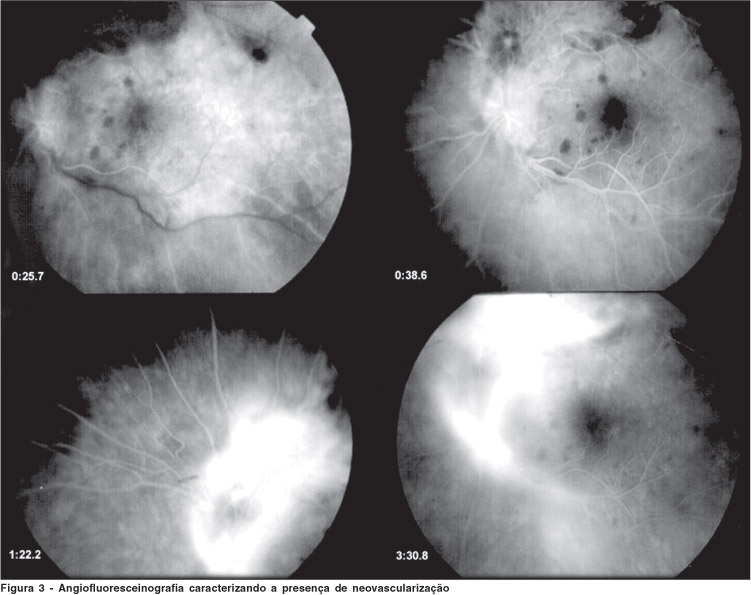

Ao exame oftalmológico apresentava acuidade visual de 20/20 no olho direito (OD) e não apresentava alterações à biomicroscopia e à fundoscopia, no olho esquerdo (OE), apresentava acuidade visual de movimentos de mãos, e à biomicroscopia presença de precipitados ceráticos (pKs) granulomatosos, reação de câmara anterior com 2+ de células e 2+ "flare". À fundoscopia apresentava lesão retiniana necrosante, branco-amarelada, em arcada temporal superior com borramento das bordas da papila, presença de hemorragias superficiais perilesionais e vitreíte leve (Figura 1). Diante do quadro foi feita hipótese diagnóstica de retinocoroidite por toxoplasmose, e iniciado tratamento específico para toxoplasmose (sulfadiazina + pirimetamina + ácido folínico). O paciente evoluiu com melhora do quadro ocular, sendo que após 4 semanas de tratamento apresentava acuidade visual de 20/200 no olho esquerdo. Ao exame fundoscópico mostrou delimitação da lesão retiniana (em cicatrização) com piora das hemorragias e aparecimento de exsudatos algodonosos e neovascularização adjacente (Figura 2). O paciente foi submetido ao exame de angiofluoresceínografia sendo observados hipofluorescência na fase venosa precoce (área de necrose) e vazamento na fase tardia em região papilar e peripapilar, caracterizando presença de neovascularização neste local (Figura 3). Optou-se pela manutenção do tratamento específico para toxoplasmose e observação semanal, e o paciente evoluiu com melhora da acuidade visual para 20/125, e regressão espontânea das hemorragias e dos neovasos (Figura 4).